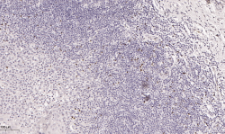

FOXP3 Rabbit Monoclonal antibody[4C7D6]

IHC    1/200-1/1000